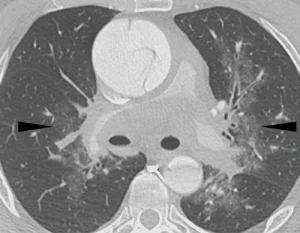

Do nguồn gốc phôi thai học chung của gốc động mạch chủ và động mạch chủ lên với động mạch phổi, nên tồn tại một đoạn ngắn của lớp ngoại mạc chung ở động mạch chủ và động mạch phổi. Đôi khi có thể thấy bóc tách type A lan rộng thành tụ máu lớp ngoại mạc dọc theo các động mạch phổi chính (main pulmonary arteries) với mức độ chèn ép khác nhau và xuất huyết nhu mô phổi trong vùng phân bố quanh mạch máu phế quản (peribronchovascular distribution) (Hình 16). Tình trạng này thường kết hợp với khó thở (shortness of breath)—liên quan đến thuyên tắc phổi—và có thể dẫn đến việc thăm khám lâm sàng hướng đến thuyên tắc phổi và không nghĩ đến hội chứng động mạch chủ cấp (AAS).

Hình 16c. Bóc tách động mạch chủ cấp có xuất huyết lớp ngoại mạc (adventitial hemorrhage) lan đến lớp ngoại mạc của động mạch phổi ở bệnh nhân nam 52 tuổi có tiền sử van động mạch chủ hai mảnh (bicuspid aortic valve), nhập viện vì đột ngột đau ngực dữ dội lan ra lưng và bụng. (c) Hình chụp CT mạch máu mặt phẳng axial (cửa sổ phổi) cho thấy các tổn thương kính mờ (ground-glass opacities) (các đầu mũi tên) xung quanh các động mạch phổi ở rốn phổi hai bên gần trung thất, phù hợp với xuất huyết phổi (pulmonary hemorrhage) quanh phế quản mạch máu.